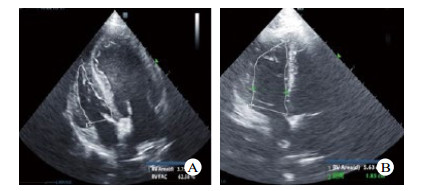

造模前后FAC、SV基线水平时差异均有统计学意义(P < 0.05),提示是ARDS本身造成的影响。PEEP递增时,造模后的SV、TAPSE低于造模前,差异有统计学意义(P < 0.05)。PEEP递增时,造模后TAPSE、SV先增大后减小,差异有统计学意义(P < 0.05)。其中SV分别在PEEP =4 cmH2O及10 cmH2O时最大;TASPE变化反复波动,见表 2。如图 2所示,造模后SV和Cstat随PEEP增加其变化趋势比较,SV和Cstat呈现同向变化关系。

| A、B中细白线勾勒图形为右室切面内腔面积大小比较,与A图比较,B图右心室腔显著扩张 图 3 造模前后犬心脏心尖四腔心超声切面 Fig 3 Comparison of echocardiography before and after modeling |